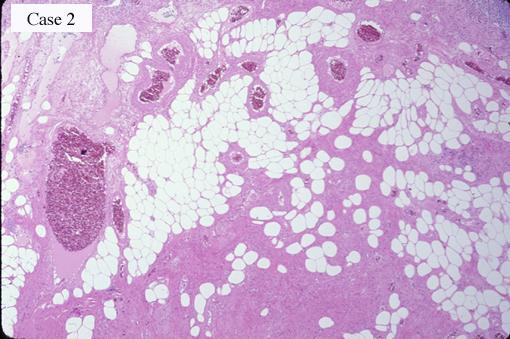

Two cases of angiolipoma which were removed endoscopically.

Non-epithelial tumors/Angiolipoma

Histology